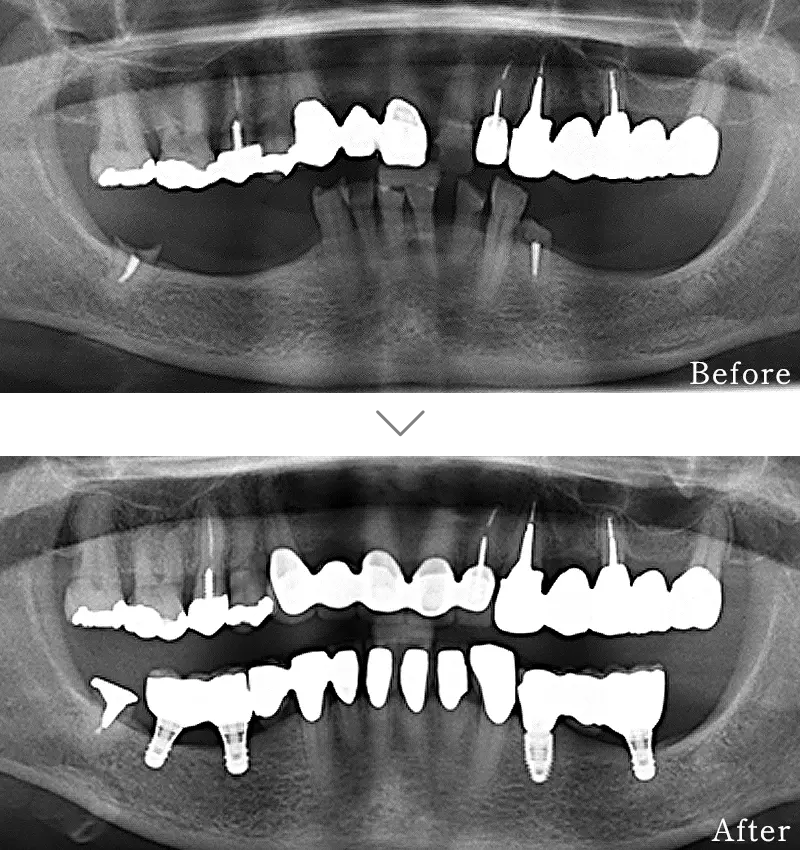

セラミック治療は、本物の歯のように白く自然な透明感のある「セラミック」という素材を用いて行う治療です。虫歯の治療で歯を削った後は、金属(いわゆる銀歯)で補う方法が一般的ですが、白い歯とかけ離れた見た目に不満を持たれる方を多いと思います。

セラミックは見た目の美しさはさることながら、硬さも天然の歯に近く、機能面でも申し分ありません。